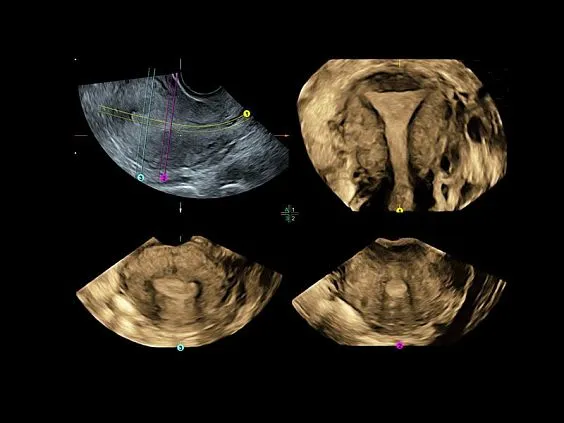

Клинические изображения

Несмотря на демократичную цену, Voluson P8 обеспечивает изображение экспертного уровня, включая поддержку 3D/4D-визуализации, что делает его востребованным в акушерстве и гинекологии. Он построен на платформе Voluson Core Architecture, которая гарантирует высокое качество двухмерной и трёхмерной визуализации, а также стабильную производительность при рутинных исследованиях.

Voluson P8 одинаково уверенно справляется как с задачами в сфере женского здоровья (оценка развития плода, диагностика патологий малого таза), так и при сканировании сердца, сосудов, органов брюшной полости и поверхностных структур. Аппарат поддерживает современные технологии обработки изображения: HD-Flow™, Speckle Reduction Imaging (SRI), CrossXBeam™, что позволяет получить максимально чёткие и информативные данные даже в сложных клинических условиях.

Простота получения 3D-изображений

Визуализация в режимах 3D/4D позволяет исследовать дополнительные анатомические плоскости, повышая вашу уверенность в диагностике.

- Визуализация плоскостей недоступных для исследования при 2D-сканировании, для более точной диагностики.

- Высокая производительность, благодаря возможности анализировать 3D данные как во время, так и после завершения исследования.

- Просмотр и обработка объемных изображений в разных плоскостях или с использованием разных режимов сканирования.